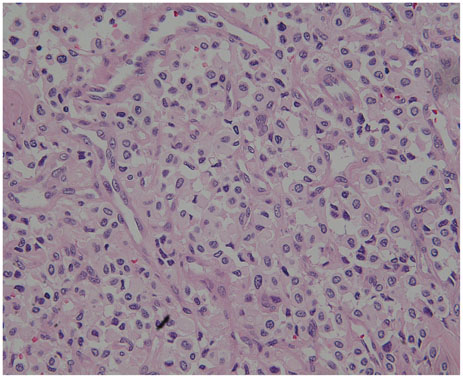

- Hemangioblastoma (HB) of the central nervous system may occur sporadically or in association with von Hippel-Lindau (VHL) disease. Disseminated HB means malignant spread of the original primary HB without local recurrence at surgically resected site. It has been rarely reported previously, and rarer especially without VHL gene mutation. We report a case of disseminated HB without VHL disease. A 59-year-old man underwent a surgery for total removal of a cerebellar HB. From five years after the surgery, multiple dissemination of HB was identified intracranially and he subsequently underwent cyberknife radiosurgery. The lesions got smaller temporarily, but they soon grew larger. Nine years after the initial surgery for cerebellar HB, he showed severe back pain. His magnetic resonance image of spine revealed intradural extramedullary mass at T6-7 level. Complete surgical removal of the mass was performed and the pathological diagnosis was identical to the previous one. He had no evidence of VHL disease. And there was no recurrence of the tumor at the site of the original operation. The exact mechanism of dissemination is unknown, but the surgeon should be cautious of tumor cell spillage during surgery and prudently consider the decision to perform ventriculo-peritoneal shunt. In addition, continuous follow-up for recurrence or dissemination is necessary for patients even who underwent complete removal of cerebellar HB.